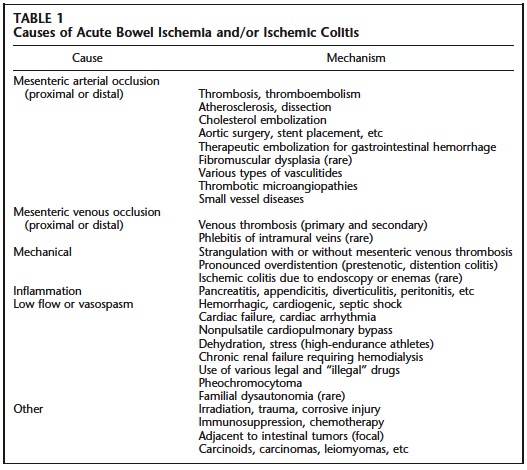

La isquemia aguda intestinal puede ser debida a oclusiones de arterias y venas y también a cuadros no oclusivos con reducción de la perfusión intestinal.

Causas más frecuentes:

- La oclusión aguda de la AMS por trombosis o émbolos es responsable del 60-70% de los casos de isquemia aguda intestinal, procediendo los émbolos del VI en pacientes con FA.

- Los cuadros no oclusivos constituyen el 20-30% de los casos. Pueden ocurrir en pacientes estado shock o pérdida de sangre por redistribución de la circulación sanguínea, pero también puede acontecer en pacientes con feocromocitoma, Sd de disautonomia familiar, atletas (deshidratación + estrés). Suele afectar al colon izquierdo, aunque esto es variable.

- La trombosis de la VMS suponen el 5 – 10% aprox.

Oclusión arterial:

La oclusión aguda de la AMS por trombosis o émbolos es responsable del 60-70% de los casos de isquemia aguda intestinal, procediendo los émbolos del VI en pacientes con FA.

La trombosis aguda de las arterias mesentéricas es menos frecuente que la embolia pero su pronóstico es más grave. Se asocia con placas de ateromas calcificadas. La oclusión de origen embólico de las arterias mesentéricas tiene un peor pronóstico, ya que el territorio afectado (intestino delgado y colon derecho) es mayor.

Existen otras muchas causas (ver tabla) que pueden producir oclusión arterial, como por ejemplo las vasculitis y el sindrome antifosfolípido.

Oclusión venosa mesentérica

La trombosis venosa mesentérica es más infrecuente y representa el 5 – 10 % de todos los casos de isquemia intestinal aguda. Las oclusiones de las venas mesentéricas pueden ser primarias o secundarias (inflamación, neoplasia, hipercoagulabilidad como embarazo o uso de anticonceptivos orales). Tienen mejor pronóstico que las de causa arterial.

Isquemia mesentérica no oclusiva o por bajo gasto:

La isquemia aguda en el intestino también puede ser causada por la reducción no oclusiva del suministro sanguíneo mesentérico (20 – 30 % de todos los casos).

Otras estiologías:

Hay que tener en cuenta la obstrucción intestinal, la cual puede complicarse y producir una isquemia intestinal causada principalmente por el compromiso de la circulación venosa tanto por compresión, debida a la estrangulación de las venas, como por una trombosis sobreañadida. Esto puede verse en hernias estranguladas, vólvulos o invaginaciones. La sobredistensión existente en el asa pre-estenótica también puede producier isquemia. Son frecuentes en el colon, raras en el intestino delgado.

En el contexto de la inflamación que producen enfermedades como la pancreatitis, apendicitis, diverticulitis o peritonitis puede desarrollarse también una isquemia intestinal. En la pancreatitis, la isquemia suele afectar al colon transverso o las flexuras hepática y esplénica.

Existen otras muchas causas de isquemia intestinal: arterioesclerosis, traumatismo, cáncer, radiación, inmunoterapia, fármacos, drogas (cocaína, heroína), etc.